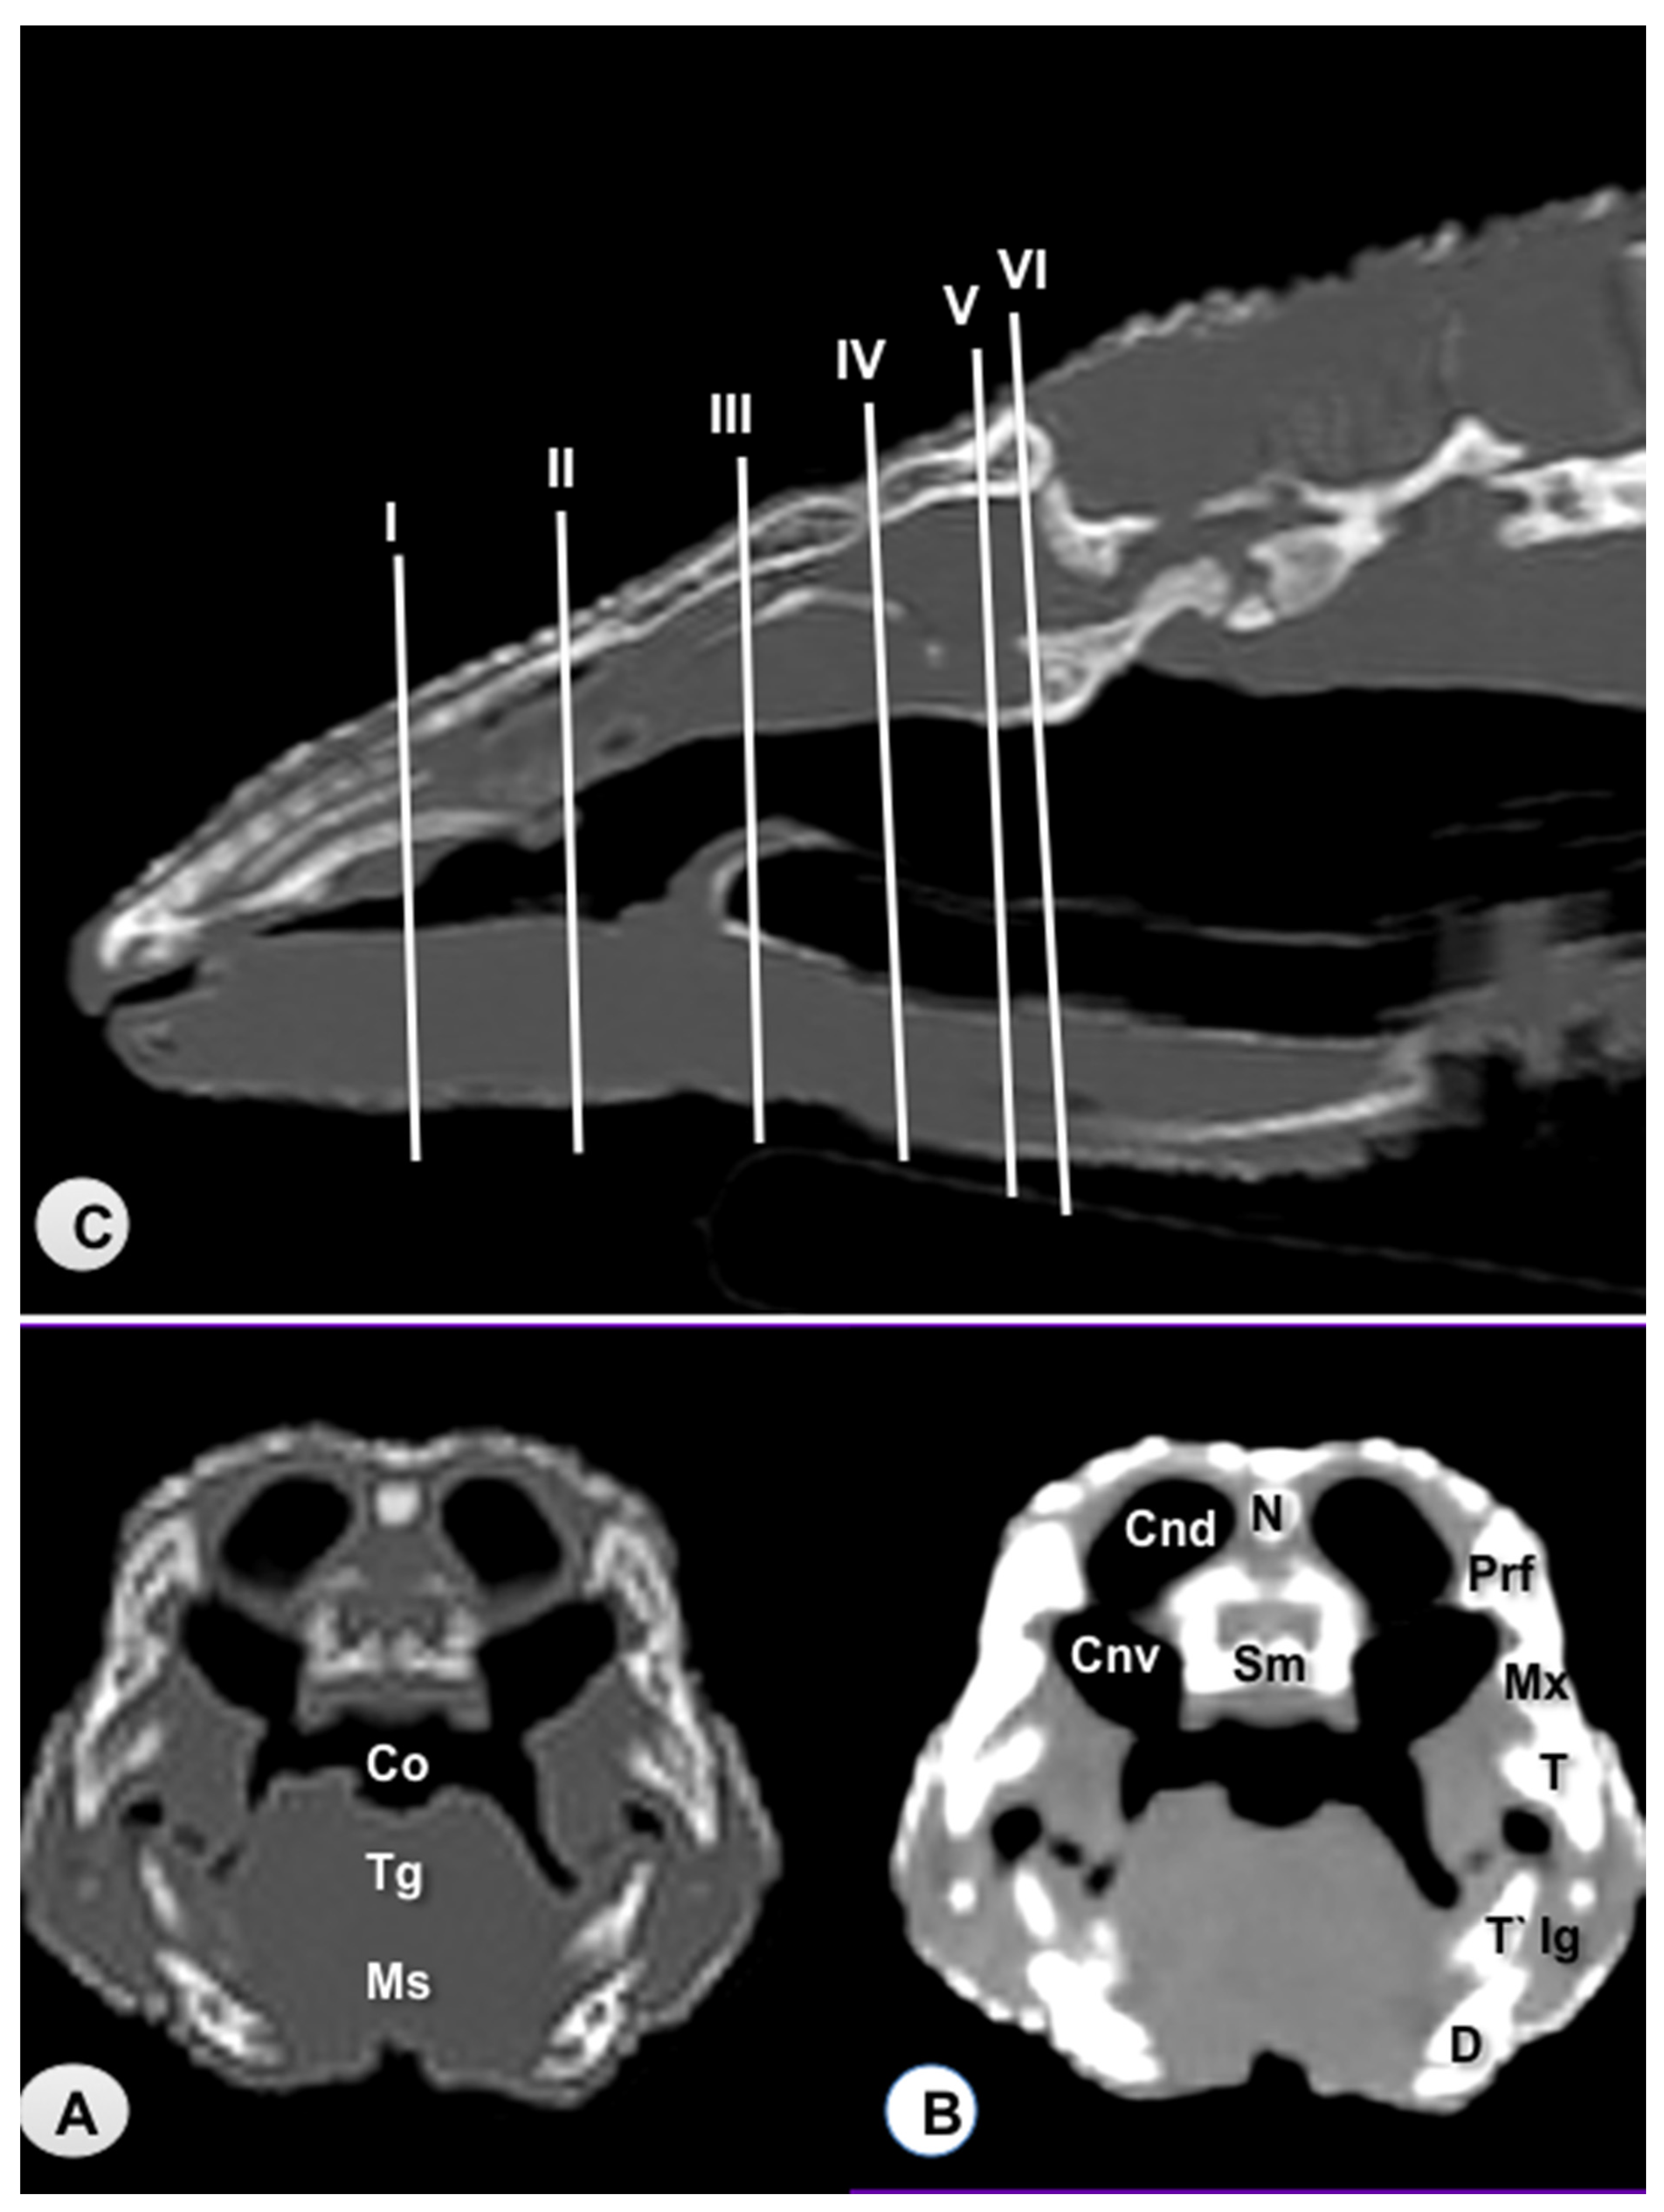

3.1. Transverse Computed Tomography Images